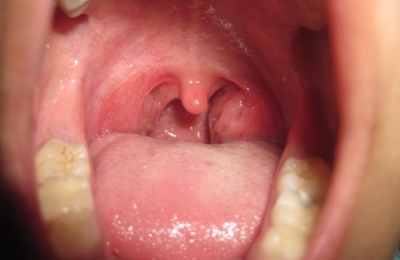

Тонзиллит представляет собой воспаление небных миндалин, которое может быть как хроническим, так и острым.

В последнем случае речь идет об инфекционном заболевании, которое чаще всего называют ангиной, а не острым тонзиллитом.

Тонзиллит – это не только причина боли в горле (она отмечается еще при ларингите и фарингите), но и фактор риска тяжелых осложнений таких, как ревматизм (в первую очередь страдает сердце и суставы) и гломерулонефрит (поражаются почки).

исчезновение патологического секрета и гноя с небных миндалин

- уменьшение красноты и инфильтративных процессов на дужках и миндалинах